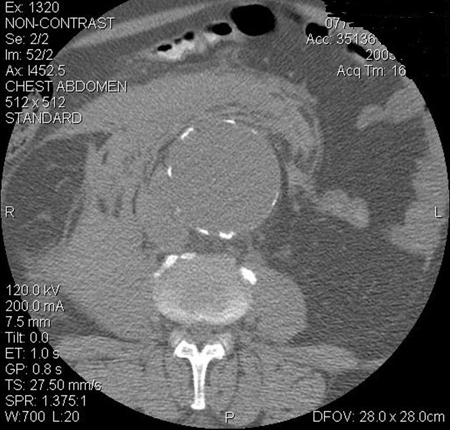

CT scan of a ruptured abdominal aortic aneurysm

University of Michigan, specifically the cases of Dr Gilbert R. Upchurch reflecting the Departments of Vascular Surgery and Radiology